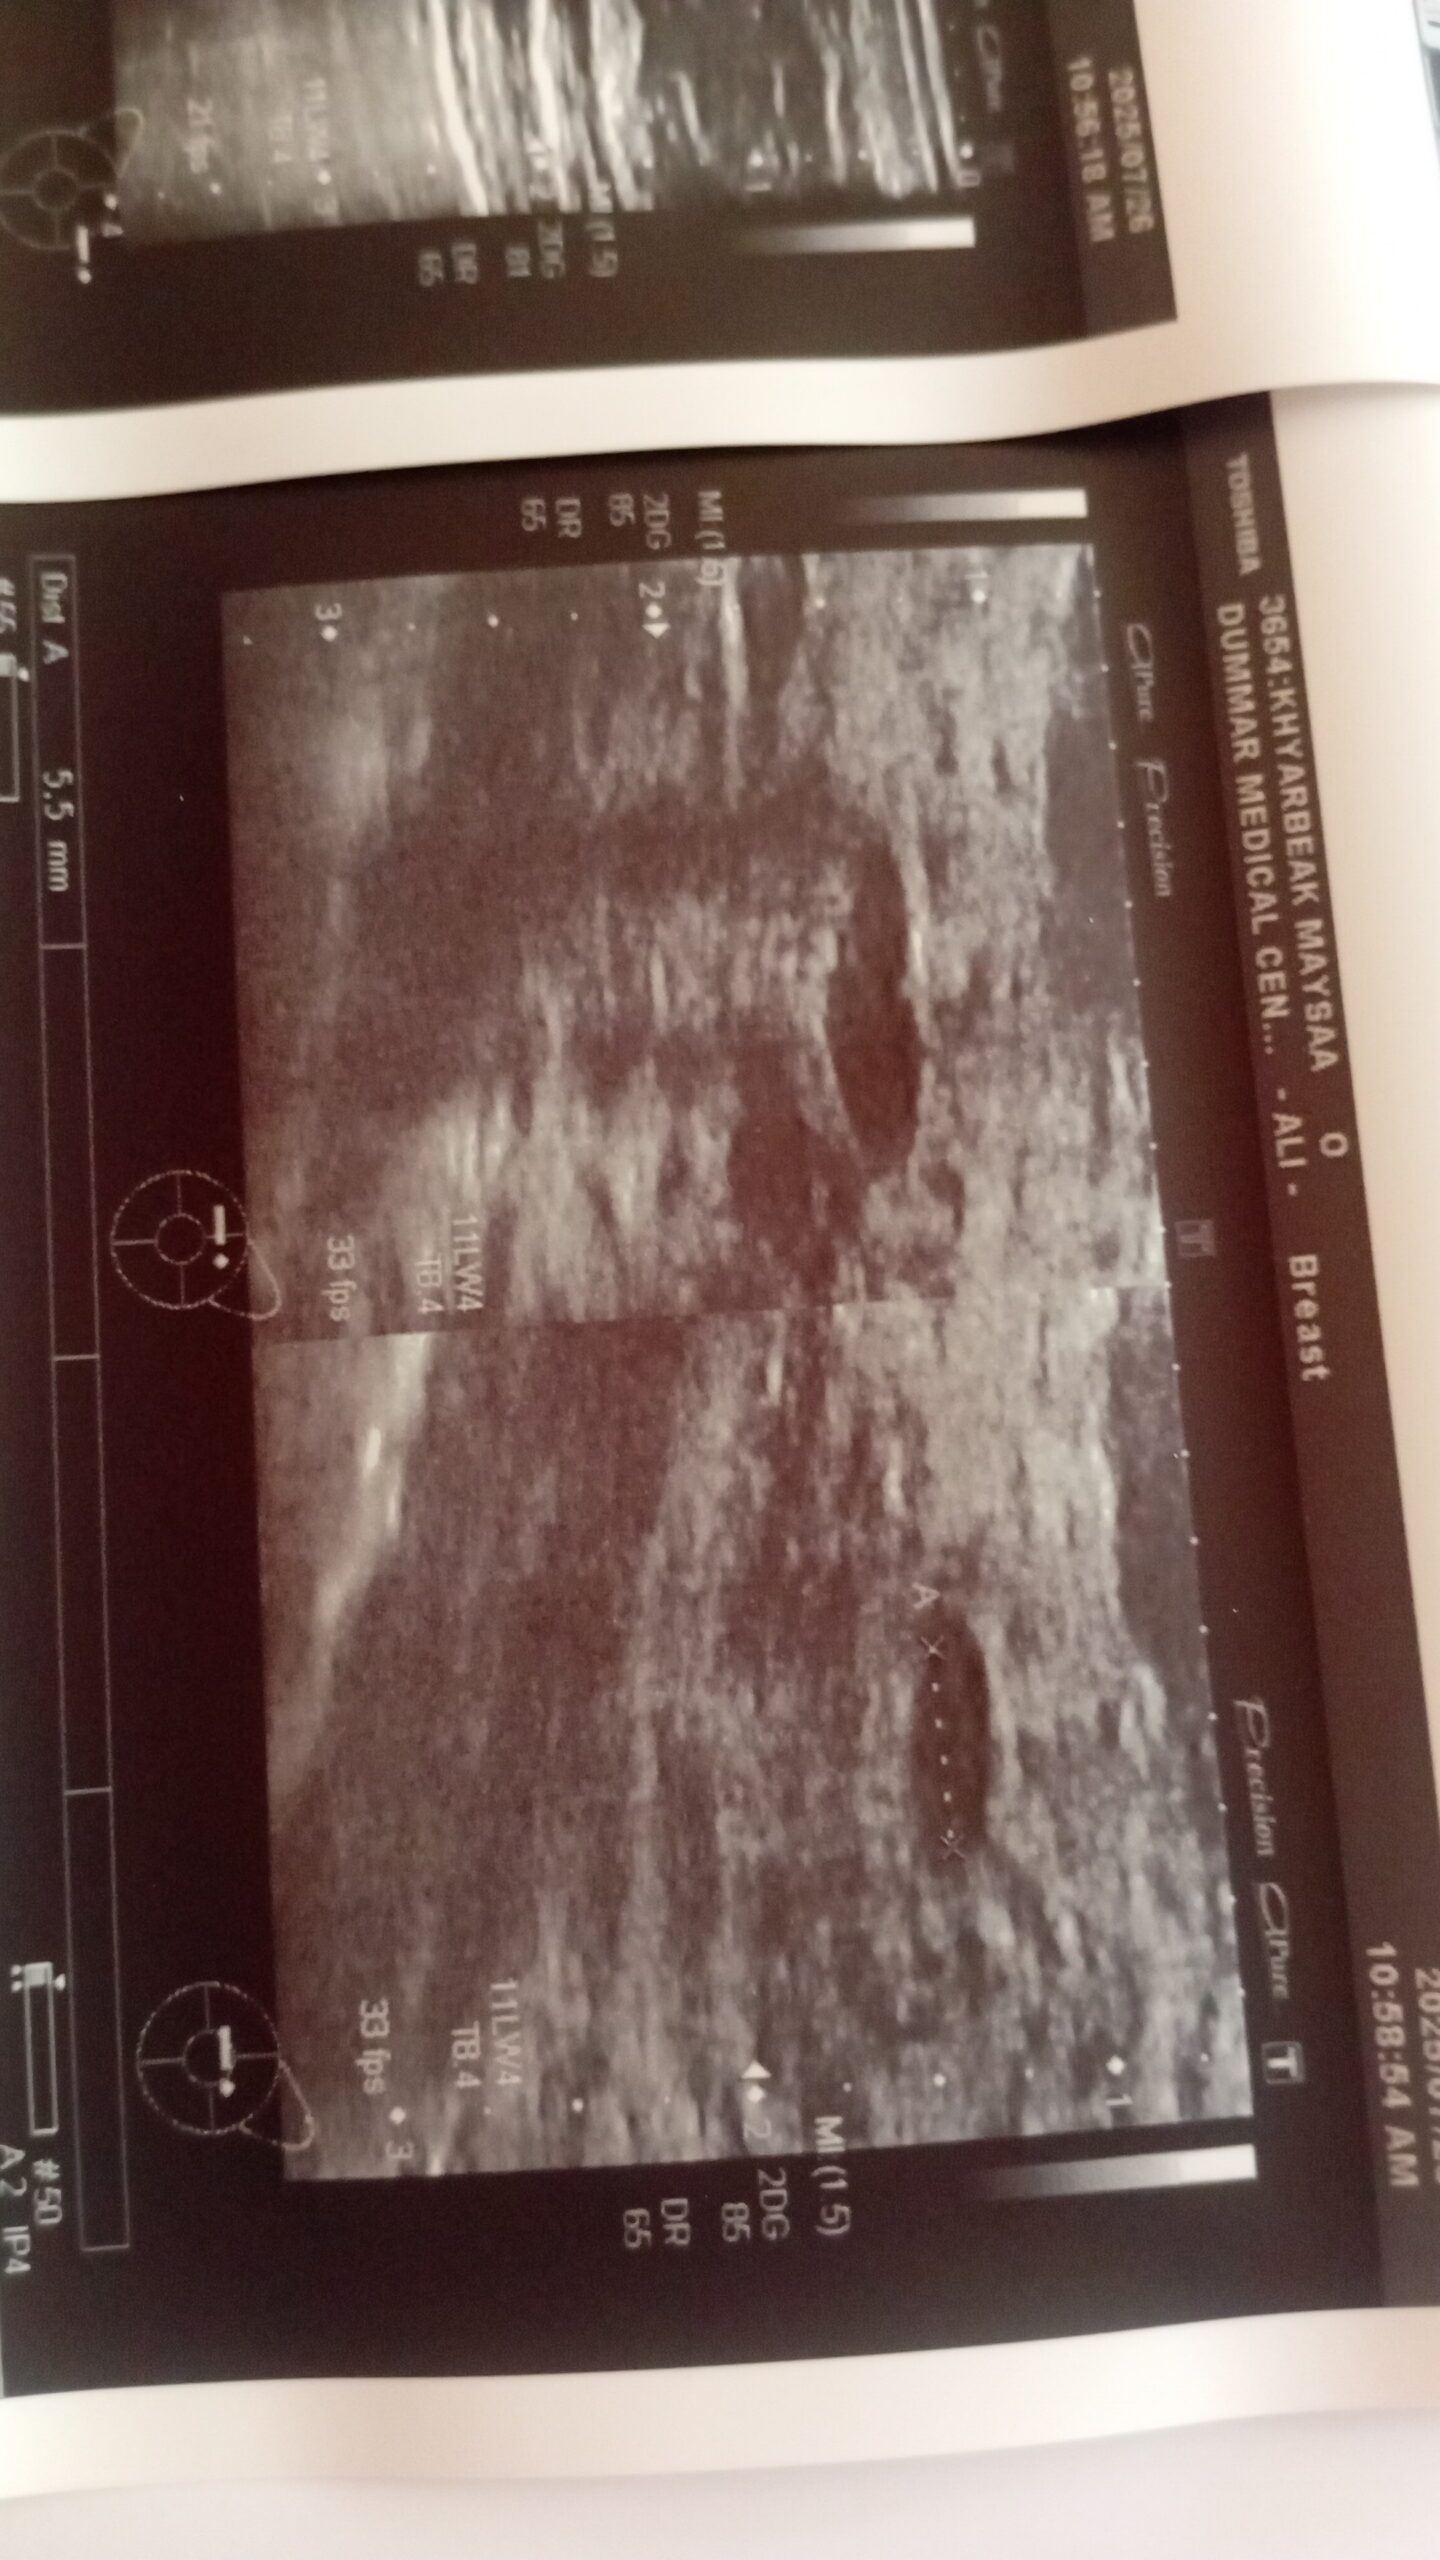

عادة تبدأ السيدة المصابة بالإحساس بكتلة دائرية وصلبة صغيرة الحجم تتحرك بسهولة بين الأصابع. وممكن أن تزداد حجما مع الوقت لتصل إلى 2 أو 3 سم، وأحيانا تصل إلى أكثر من 5 سم. وهي في معظم الأحيان غير مؤلمة. وممكن أن يكون لدى بعض النساء أكثر من ورم في نفس الثدي أو في كلا الثديين. إن تشخيص هذا الورم بصورة عامة أمر سهل. فخلال الفحص الطبي، مع إجراء الصور اللازمة، مثل صورة السونار أو الماموغرام يكون تشخيص هذا الورم ممكنا. في بعض الأحيان يكون التشخيص غير أكيد مما يتطلب عمل خزعة عن طريق إبرة صغيرة.

دكتور بليز فيك تخبرني اش احتاج بضبط ؟ عندي كذا ورم ليفي غدي بس اخر مره عملت هذي اشعه ولسع مادخلت للدكتور لان موعد بعيد شوي وحابه اطمن